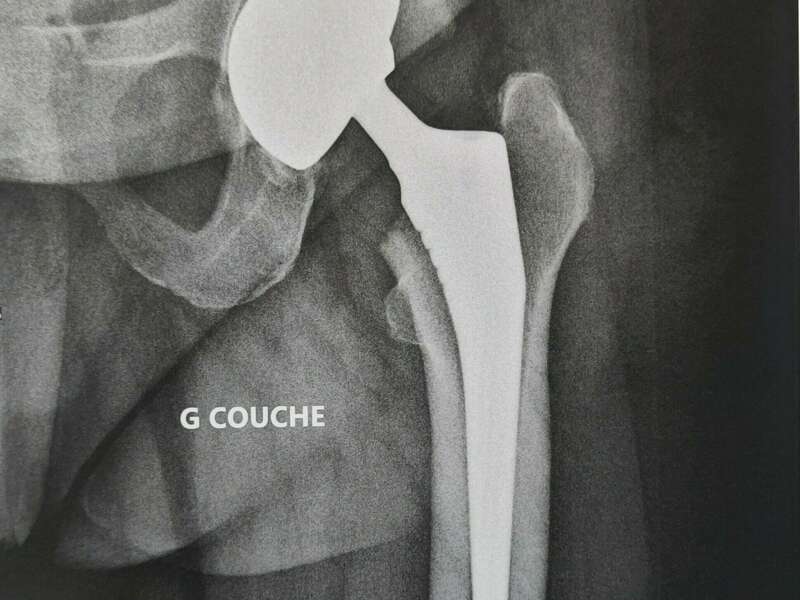

Album photo